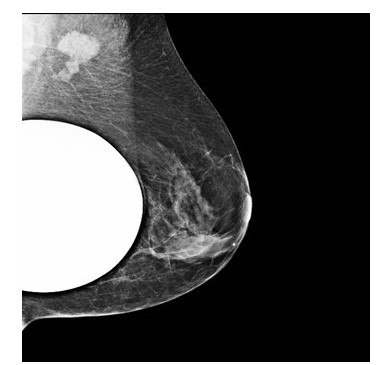

Presentamos el caso de una paciente 53 años, quien consulta refiriendo aumento de volumen en región axilar izquierda de 1 año de evolución. Al examen físico sin evidencia a la palpación de lesiones mamarias, se aprecia en la axila izquierda plastrón ganglionar de 4 cm de diámetro movible, no fijo a estructuras vecinas. En los estudios realizados, como lo son mamografía, eco mamario y resonancia magnética de ambas mamas con gadolinio en marzo 2022, solo se observa, la presencia de lesión de ocupación de espacio en axila izquierda, sugestivo de plastrón ganglionar, sin lesiones subclínicas en las mamas (Figura1,2,3)

Al examen físico mamas grandes asimétricas, presencia de cicatrices de mamoplastia de aumento, portadora de implantes mamarios, no se palpan tumores mamarios, y en la axila izquierda plastrón ganglionar de 4 cm. de diámetro duro movible que no infiltra piel. En vista de los hallazgos clínicos y de imágenes se procedió a realizar biopsia ecoguiada con aguja gruesa de corte, el 11/ 04/ 2022, reportando la anatomía patológica biopsia ap 3542 22, carcinoma ductal invasor grado II, ausencia de componente de carcinoma in situ, desmoplasia acentuada, con resultados para inmunohistoquímica biopsia ap. 3542 22 RE, + RP + ERB 2 neu negativo KI 67: 10 % subtipo molecular intrínseco tipo luminal A (Figura 4).